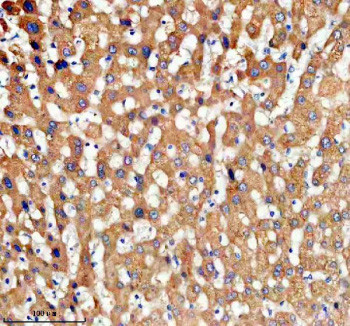

Adding 0.2 ml of distilled water will yield a concentration of 500 ug/ml. TDO2 antibody detects tryptophan 2,3-dioxygenase, a heme-dependent enzyme that catalyzes the first step of the kynurenine pathway, converting L-tryptophan to N-formylkynurenine. The UniProt recommended name is Tryptophan 2,3-dioxygenase (TDO2). This enzyme regulates systemic tryptophan levels and influences serotonin biosynthesis, immune tolerance, and NAD+ metabolism.Functionally, TDO2 antibody identifies a homotetrameric enzyme that incorporates molecular oxygen into the indole ring of tryptophan. The enzyme is predominantly expressed in liver but is inducible in many tumor types. TDO2 activity shapes the immune microenvironment by depleting tryptophan and generating immunosuppressive kynurenine metabolites. This mechanism contributes to tumor immune evasion and cancer progression.The TDO2 gene is located on chromosome 4q32.1 and encodes a 406-amino-acid protein with a conserved heme-binding pocket. Its expression is transcriptionally induced by glucocorticoids, stress, and pro-inflammatory cytokines. Elevated TDO2 levels have been reported in hepatocellular carcinoma, glioblastoma, and melanoma, positioning it as a therapeutic target in oncology. TDO2 also regulates neuroactive tryptophan metabolites implicated in mood disorders and neurodegeneration.Pathologically, upregulation of TDO2 disturbs immune cell proliferation and antigen presentation through depletion of tryptophan and accumulation of kynurenine. Inhibiting TDO2 restores T-cell activity and is an emerging immunotherapeutic strategy complementary to checkpoint blockade. In metabolic studies, altered TDO2 activity links to hepatic inflammation and altered redox homeostasis.TDO2 antibody is widely applied in cancer immunology, metabolism, and neurobiology research. It is suitable for immunoblotting, immunohistochemistry, and enzyme assays detecting TDO2 expression or localization. NSJ Bioreagents supplies high-quality TDO2 antibody reagents validated for use in relevant metabolic and immunological assays.Structurally, tryptophan 2,3-dioxygenase possesses a catalytic heme group coordinated by a proximal histidine. Substrate binding induces conformational changes that enhance dioxygen activation. This antibody supports biochemical and translational studies targeting TDO2 for metabolic modulation and immunotherapy development.

| Application: | WB, IHC, FC, ELISA |